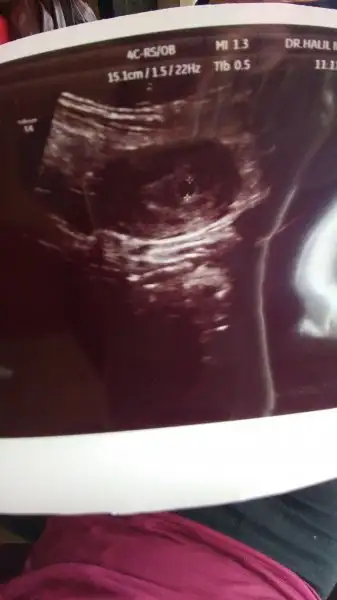

Birde böyle sorunlar mi varmış ilk defa duyuyorum neler öğreniyor insanKızlar internette okumuştum kesenin yusvuvsrlak olması gerekiyomuş benim ilk baktığımızda yusyuvarlaktı daha sonra gittiğimde değişikti bi bakar mısınız ? Bozulmuş kese mi benim ki

Benim kesem duzensizdi ama senin ki normal görünüyor zaten ole bisey olsa doktorun solerdi kafaya takma daha koskoca , 8 ayın var baciMKızlar internette okumuştum kesenin yusvuvsrlak olması gerekiyomuş benim ilk baktığımızda yusyuvarlaktı daha sonra gittiğimde değişikti bi bakar mısınız ? Bozulmuş kese mi benim ki